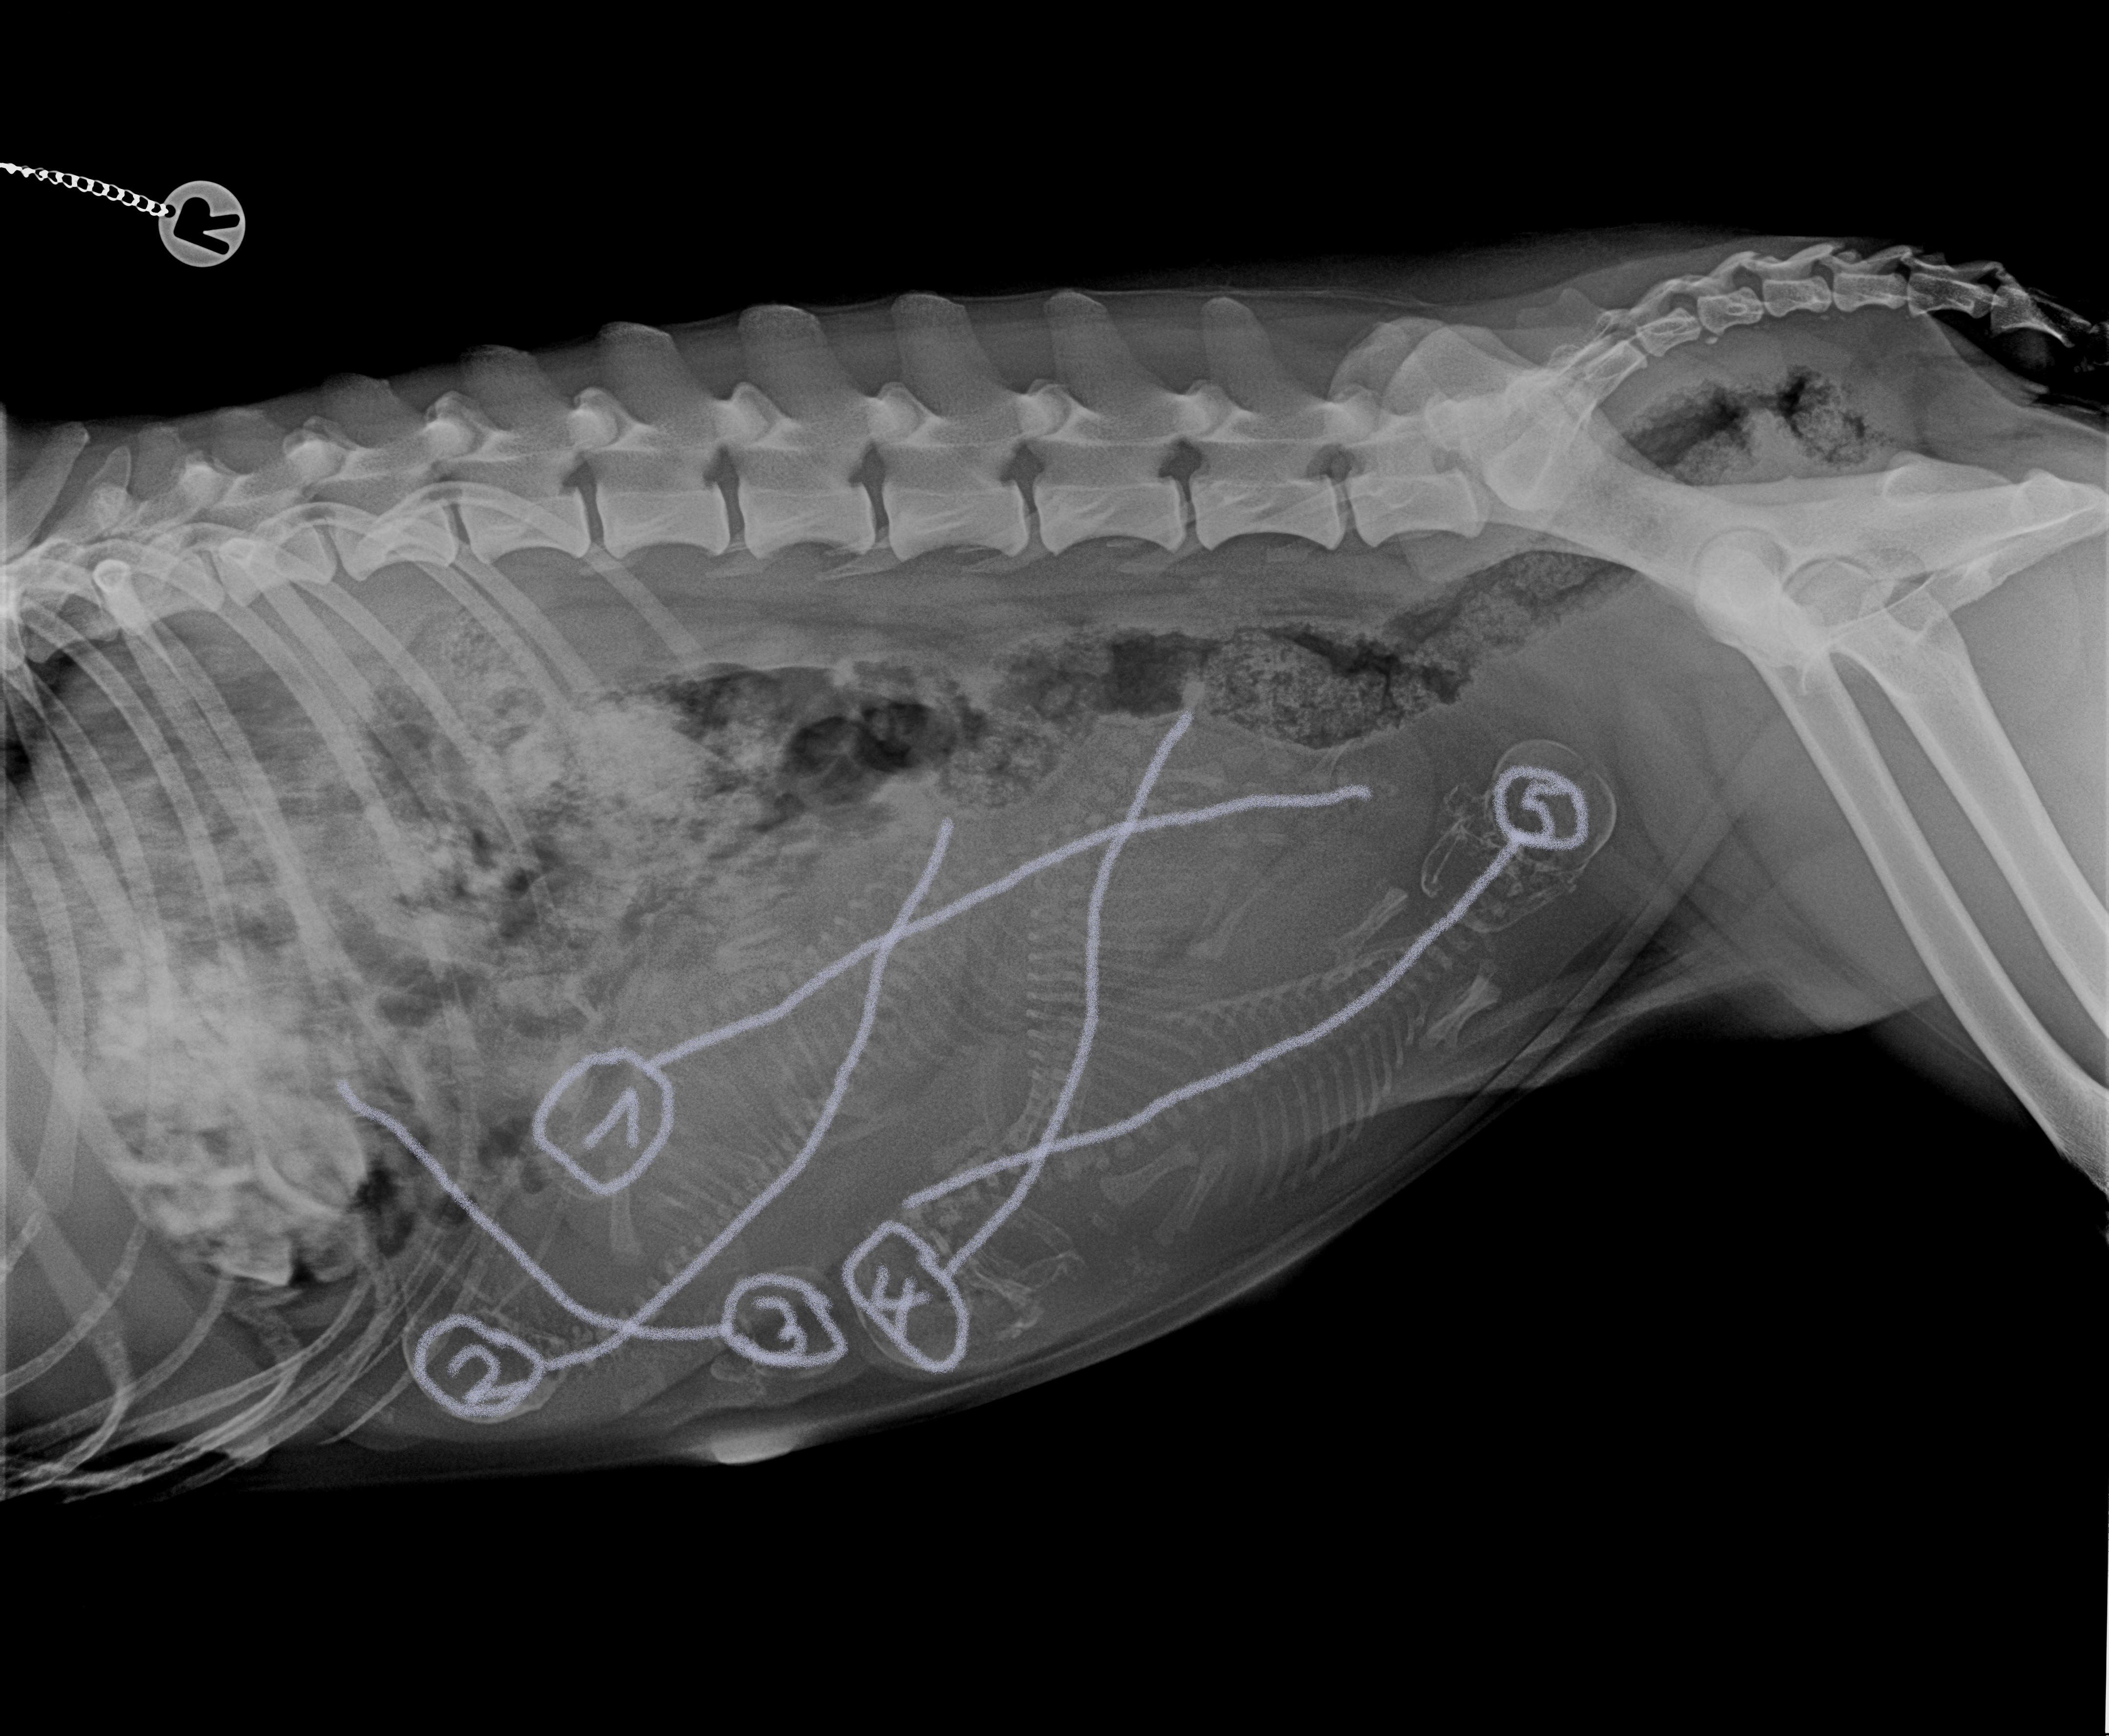

19:30 >>>>> Der Plan die noch irgendwie natürlich raus zu bekommen was sich dann auch lohnte. 18:30 >>>>> Das Röntgenbild zeigte zwei Drängler... zwei gleichzeitig im Geburtskanal. Einer Rückwärts den ich schon fühlte und ein anderer Vorwärts gerichtet.

Nun haben wir es schwarz auf weiß... Das Röntgenbild zeigte uns fünf Babys die wir nächste Woche erwarten können. Zoe geht es super und sie sieht blendend aus, in den nächsten Tagen bereiten wir uns auf die Geburt vor. Die Temperaturtabelle wird dann wieder eingefügt damit ihr alle mitlesen könnt :o)) Ein Welpe ist etwas Kleiner als die anderen, also drückt alle die Daumen das er fleißig wächst zum Geburtstermin.